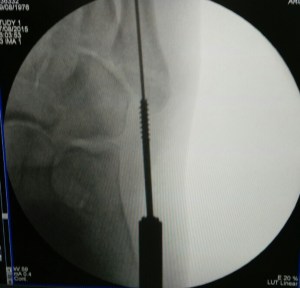

Percutaneous cannulated screw fixation of this displaced avulsion fracture of the 5th metatarsal base was performed.

This procedure is done via a small incision and guided by x-rays fluroscopy.

This is the final result: